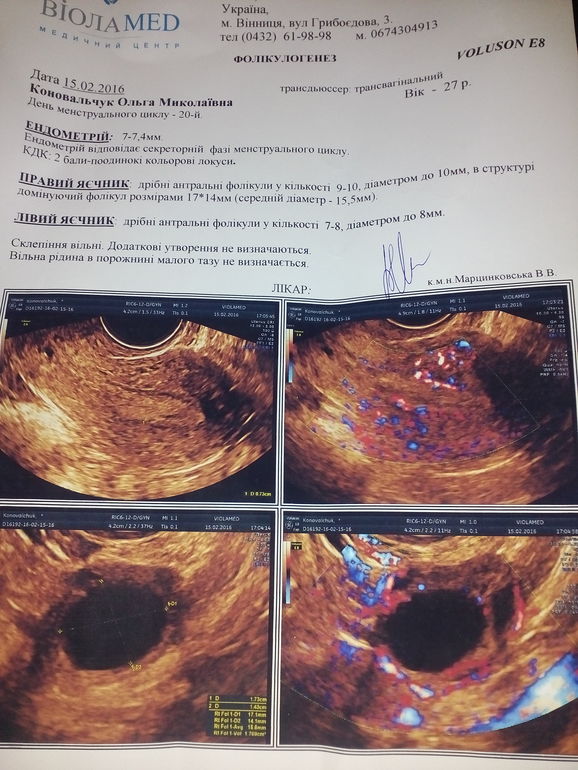

На какой день делать узи фолликулов 114 фотографий